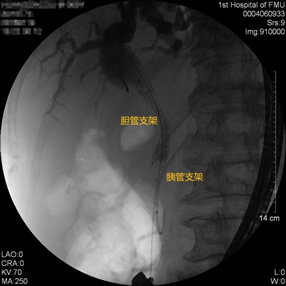

胃毕-Ⅱ术后胰管胆管双支架植入 胃毕-Ⅱ术后胆管金属支架植入